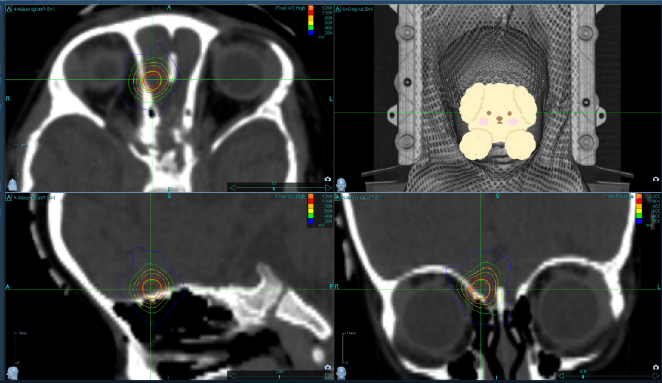

这意味着病魔已经突破了化疗方案的桎梏,而血脑屏障也将阻挡特效药GD-2单抗进入颅内,雪上加霜的是,这个新病灶离视神经和眼球非常近,常规的放疗技术无法避免视力和正常脑组织损伤。

成人放疗和儿童放疗有何区别? 儿童肿瘤患者以脑部肿瘤、软组织肿瘤、淋巴肿瘤患者居多,绝大部分儿童肿瘤都是恶性肿瘤。相较于成人,儿童的放疗更为复杂—— 放疗时患儿需要单独待在治疗室,多数患儿会因为认知不足和情绪紧张出现很多意外情况,影响放疗计划正常进行。 “因此,确切有效的镇静措施非常必要。儿童放疗不仅需要考虑疗效,更需要考虑毒副反应对生长发育的影响,毕竟,让患者有质量有尊严地活着,才是我们医者施治的终极目标。” ——金晶教授 好在“天无绝人之路”,囡囡的父母经过多方打听后了解到,中国医学科学院肿瘤医院深圳医院有位顶尖的放疗高手——金晶教授。 ❶ 保障“后方资源”到位:参与儿童MDT团队讨论,精心筹备婴幼儿的专用设备耗材,包括儿童专用心电监护仪、氧气枕、儿童专用高压留置针、儿童专用呼吸球囊、小儿型吸氧管等等。 ❷ 维护治疗流程正常进行:从CT定位室到MR定位室,全程保障安全转运;在MR限制条件下,常规生命体征测量仪器无法带入磁共振室机房,确保深度镇静下囡囡的安全…… ❸ 确保机房内部“万无一失”:评估射波刀机头行走路径,正确安放监护仪,保障监护仪正常工作;射波刀放疗时,家属和工作人员都不能陪同,采取有效措施预防囡囡坠床等问题。 点滴环节,都凝聚了团队成员的心血与汗水,只为力求儿童放疗精准无误。金晶教授表示:“不论成人还是儿童,我们深知每一次治疗都是对生命的守护,也是对精准医学的追求。” 考虑到囡囡年龄太小,整个治疗过程中,医护团队特别注重人文关怀。技师长张寅介绍道: “我们特意为囡囡打造了一个温馨的儿童游乐室,让她能在熟悉的环境中感到安心。机房内也装饰了可爱的贴纸,以消除她的恐惧感。在等待治疗期间,我们会陪她一起做手账、看动画片,帮助她转移注意力,减轻不适。” [ 儿童游乐室 ] 对于囡囡的父母而言,这段时间无疑是充满焦虑和压力的。但好在他们不是一个人在坚持,医护人员经常主动地给予安慰和支持,向他们传递信心和希望:“一切都会好转的,对囡囡要有信心。” 面对病情的复杂性,既要充分保证疗效,又要保证尽量减少视神经和颅脑的放射性损伤,还要考虑儿童放疗配合度低的特点。 医疗团队不分昼夜,查阅并比对了多个权威指南,确保剂量选择和等效生物剂量计算的合理性和准确性,争取发挥射波刀“精准雕刻放疗”和“手起刀落”疗程短的优势。 “儿童患者放疗反应的发生率和严重程度与剂量密切相关,疗效与安全性需反复斟酌,针对神经母细胞瘤这种放疗高度敏感的肿瘤,脑转移局部病灶是否有必要参照常规脑转移指南,接受高剂量放疗值得商榷。” 更是囡囡生命毅力的证明 是患者、家属与医护人员 共同抗击癌症的胜利结晶 爱,能抵抗世间万难 更能书写生命奇迹 原中国医学科学院肿瘤医院放射治疗科副主任 原中国医学科学院肿瘤医院医务处处长 北京协和医院博士生导师 深圳大学、南方科技大学硕士生导师 中国医学科学院肿瘤医院深圳医院院长助理 放射治疗科主任 主任医师 医学博士 • 临床擅长: 擅长直肠癌、胃癌、肝与胰腺胆道系统肿瘤、乳腺癌、泌尿系统肿瘤、淋巴瘤和软组织肿瘤的规范化放射治疗和多学科综合治疗。熟练掌握国内外最新的放射治疗技术,如立体定向照射、图像引导调强放疗、质子/重离子放疗、靶向治疗与免疫治疗等。 • 专家简介: 致力于放射治疗和多学科综合治疗30余年。以第一作者/通讯作者发表文章百余篇,刊登于Journal of Oncology, JAMA子刊等期刊。牵头多项全国多中心临床研究,主持国家自然科学基金面上项目3项、北京市首发重点、北京市与深圳市多项临床与转化研究课题。在北京协和医学院、深圳大学招生、带教硕博士、博士后接近三十名。 • 出诊时间:周二上午、周四下午 放射治疗科 主任医师 放射治疗科病区主任 • 临床擅长: 儿童肿瘤如淋巴瘤、肾母细胞瘤、神经母细胞瘤及软组织肉瘤,鼻咽癌、宫颈癌及食管癌综合诊疗及放射治疗。 • 专家简介: 从事放射肿瘤学临床及教学工作三十余年。兼任中国抗癌协会近距离放射治疗专业委员会常委、中国临床肿瘤协会鼻咽癌专家委员会委员、广东省医院协会放射治疗科管理专业委员会副主委。 • 出诊时间: 专家门诊:周二下午、周三上午 特需门诊:周五上午 放射治疗科病区主任(头颈肿瘤专业组) • 临床擅长: 擅长鼻咽癌、口咽癌、下咽癌、口腔癌、鼻腔副鼻窦癌、脑原发肿瘤、其他头颈少见肿瘤(腺样囊腺癌、软组织肿瘤、嗅神经母细胞瘤、生殖细胞瘤、室管膜瘤、头颈部瘢痕)的综合治疗。 • 专家简介: 医学博士,毕业于北京协和医学院临床医学八年制,毕业后就职于中国医学科学院肿瘤医院放射治疗科,现为中国医学科学院肿瘤医院深圳医院放射治疗科头颈病区主任。 • 出诊时间:周一上午、周四上午 放射治疗科 副主任医师 • 临床擅长: 鼻咽癌等头颈肿瘤放疗联合免疫治疗、成人儿童脑肿瘤精准放疗、癌症晚期姑息放疗。 • 专家简介: 专注临床工作20多年,擅长鼻咽癌、口咽癌等头颈部肿瘤调强放疗,联合化疗、靶向和免疫治疗的综合应用;熟练掌握脑胶质瘤、室管膜瘤、生殖细胞瘤等脑肿瘤的TOMO和射波刀精准放疗;娴熟应用儿童肿瘤TOMO放疗,提供儿童质子放疗咨询;善于应用射波刀CyberKnife进行脑转移瘤SRS放射外科治疗,对癌症晚期姑息放疗具有丰富的临床诊治经验。 • 出诊时间:周二上午、周四下午